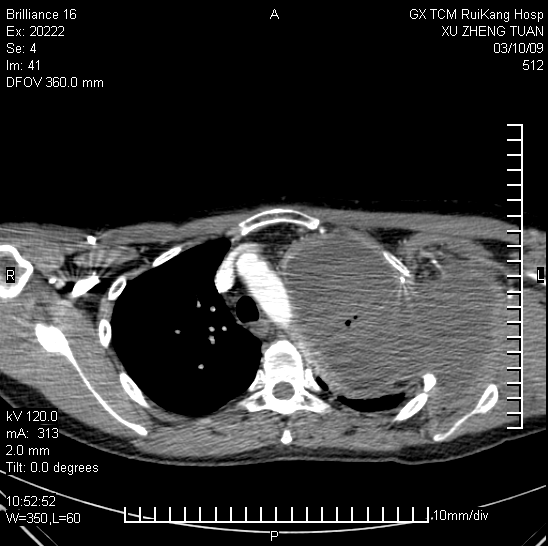

在广州工作的广西隆安人许正团,男,今年40岁,他有一个幸福的小家庭。可是,命运在作弄着他。6年前,他发现左胸肿物1月后入住广州一家肿瘤医院,并于同年11月进行手术切除。当时肿块像鸡蛋大(5×4.5×2立方厘米)。病理检查为良性。许先生本以为手术后就万事大吉了。谁知一年后,他又发现左胸壁肿物又在长,当时他还没未予以重视。随后肿物又逐渐增大,自己已经感觉胀痛了,并感到左上肢不能上抬及后转。08年底肿瘤疯长到20×20平方厘米,像成人手掌这么大了,这时肿瘤已经把左肺都挤扁了,连喘气都感到困难。这时徐先生又回到原来手术的医院就诊。经过CT片检查,专家无奈地说:这种病要彻底治疗只能把左手及胳膊全切掉才能保住命。专家还说:其实能帮你提出这个方案的已经很大胆了,没有医生愿意牺牲这么大的一个创伤,而且也不能确保肿瘤不复发。许先生一听都吓懵了。他想:这样我就成了个残疾人了吗?太可怕了……。许先生说:“确实那时候,我很难面对,心里也很绝望。但是我就想,想尽所有的办法,再多去几家医院看看。随后我又去了上海找了最权威的肿瘤医院和专家,得到的答复基本上是一致的。实际上我从上海回来的时候,已经感到没有别的选择,准备做出最痛苦的决定:割掉我的左臂和手了。”

2009年2月初,许正团就抱着试试看的想法来到了广西瑞康医院。该院肿瘤一区主任练祖平教授和白广德教授看了患者带来的病历资料,他们认为,巨大肿瘤可采用射波刀放射治疗和氩氦刀冰冻治疗。先将巨大肿瘤逐渐杀灭后,遗留下来的肿瘤坏死组织再通过中药在体内慢慢吸收,同时运用中医特色防止肿瘤的复发。专家们提出了这个全新的治疗方案。许先生感到很震惊。此时他感到自己有救了……。他决定试一试。这时,许先生住进了瑞康医院,开始长达两个月的治疗。因患者胸部的肿瘤太大了,医生决定采用射波刀立体定向放疗联合氩氦刀微创冷冻治疗:位于左锁骨以下向左侧胸壁、胸腔侵犯的肿瘤,用氩氦刀冷冻治疗;位于左锁骨以上向左肺尖及左肩、左颈侵犯的肿瘤,用射波刀治疗。经过多次的治疗,终于将巨大肿瘤细胞杀灭了。住院两个月后,许先生在配合健脾益气、益肝补肾的中药内服为主,主要是尽快恢复两刀治疗所致的机体创伤。两刀治疗结束后,中药则以解毒散结、益气通络为治法,目的是消除机体形成肿瘤内环境因素,阻断肿瘤的生长,防治肿瘤的复发,初期尚配合针灸以促进左上肢机体功能恢复。自2009年5月后,患者已经开始回到原工作岗位上班,并坚持在门诊服用上述中药调理。

至今历时2年半时间,经过3次CT和磁共振检查,均提示该肿瘤逐渐缩小,最后一次复查(2011年8月15日CT)见肿瘤已经缩小至5cm×3cm,仍为坏死组织,左肺已经完全复张,左上肢功能已经完全恢复,没有发现新病灶。